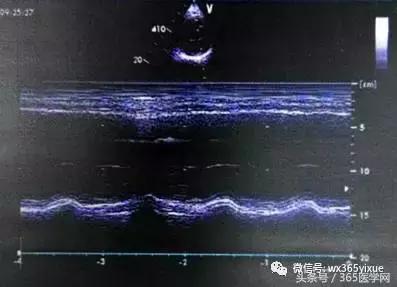

心脏彩超

EF31% 左房、左室明显扩大,左室前壁心肌梗死,左室壁运动搏幅普遍减低,左室收缩功能减低。